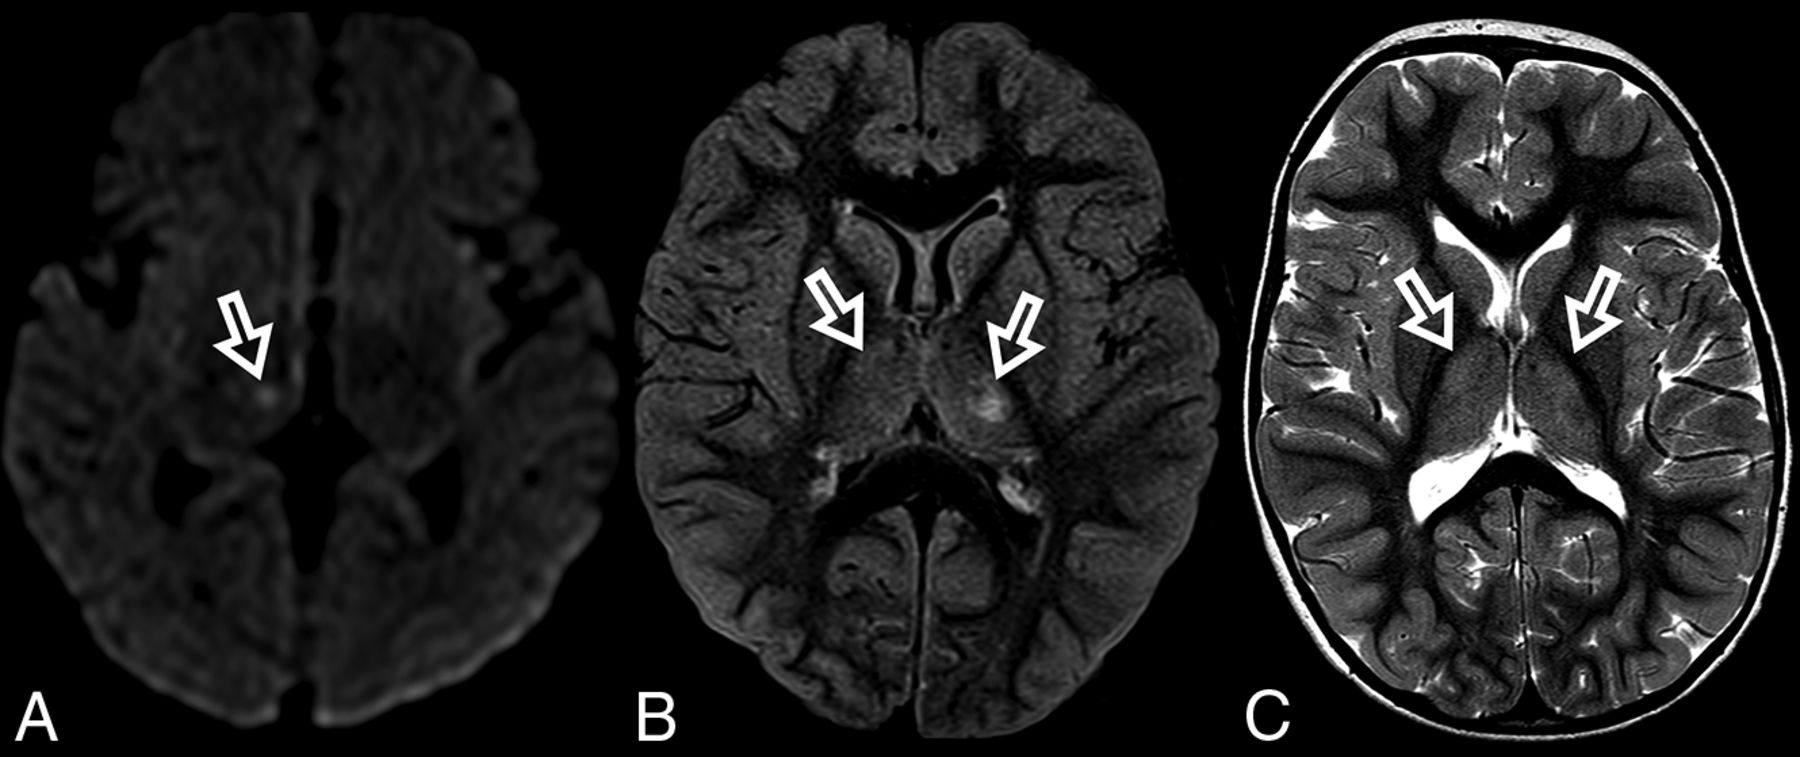

At diagnosis, brain MR imaging findings were abnormal in most patients (n = 12, 92%). The most common brain MR imaging findings were unilateral or bilateral perirolandic signal changes (n = 7, 54%) (Fig 1) and unilateral or bilateral thalamic signal changes (n = 10, 77%) (Fig 2). Perirolandic signal abnormalities were unilateral in most cases (n = 5, 71%) and were more frequently seen only affecting the precentral or both the pre- and postcentral gyri. Half of the thalamic changes were unilateral (n = 5, 50%). Simultaneous perirolandic and thalamic signal changes occurred in 6 patients (n = 6, 46%). An association of EPC (clinically/EEG) and perirolandic signal changes was present in 6 patients (n = 6, 75%), and an association of EPC (clinically/EEG) and thalamic signal changes, in 7 patients (n = 7, 87.5%). Two patients with EPC (clinically/EEG) did not present with perirolandic signal abnormalities. The findings positive for lesions overall were on the DWI of 10 patients (n = 10, 83%), on the T2WI of 9 patients (n = 9, 75%), and on FLAIR of 7 patients (n = 7, 58%). In 4 patients, DWI was the only sequence with abnormal findings. The occipital lobe was affected in the early brain MR imaging in 2 patients (n = 2, 15%). Signal changes in other brain regions were found in 5 patients (n = 5, 42%), involving multiple regions, namely the cerebral white matter, insula, putamen, caudate nucleus, fornix, cerebellar vermis, and also the frontal and occipital lobes. One patient did not present with either perirolandic or thalamic changes but instead presented with a diffuse pattern similar to that of leukoencephalopathy, with restricted diffusion in the white matter and white matter tracts (Fig 3). Three patients had an abnormally high lactate peak on MR spectroscopy. None of our patients had ASL or other perfusion-weighted imaging at the time of diagnosis. T1 and T2* imaging and SWI had negative findings at the time of diagnosis.

Perirolandic sign in 4 different patients with POLG-related disorders (A, An 8-month-old female), (B and C, A 3 year-old-male), (D, An 1-year-old male) and (E and F, A 9-month-old female). Signal changes around the central sulcus were variable with varying degrees of conspicuity. A, T2WI. Signal changes are subtle and focal, evident only in the left precentral gyrus (open arrows). B, T2WI. Signal changes are subtle and focal, evident in the left pre- and postcentral gyrus (open arrows), but more conspicuous in the DWI (open arrows, C). D, DWI. Linear signal changes involving mainly the cortex surrounding the right central sulcus (open arrows). E and F, DWI and ADC map, respectively. Marked signal changes in both right pre- and postcentral gyri.

The MR imaging appearance of the perirolandic sign was varied. Signal changes involved both the pre- and postcentral gyri, more commonly in the precentral gyri. The conspicuity of the perirolandic sign was also variable (Fig 1). In the more notable cases, signal changes were ribbon-like following the course of the gyri, which were readily detectable as T2 hyperintensities and restricted diffusion. DWI was the most sensitive MR imaging sequence to detect signal changes and, therefore, should always be included in the protocol and carefully evaluated when a case of POLG-RD is suspected.